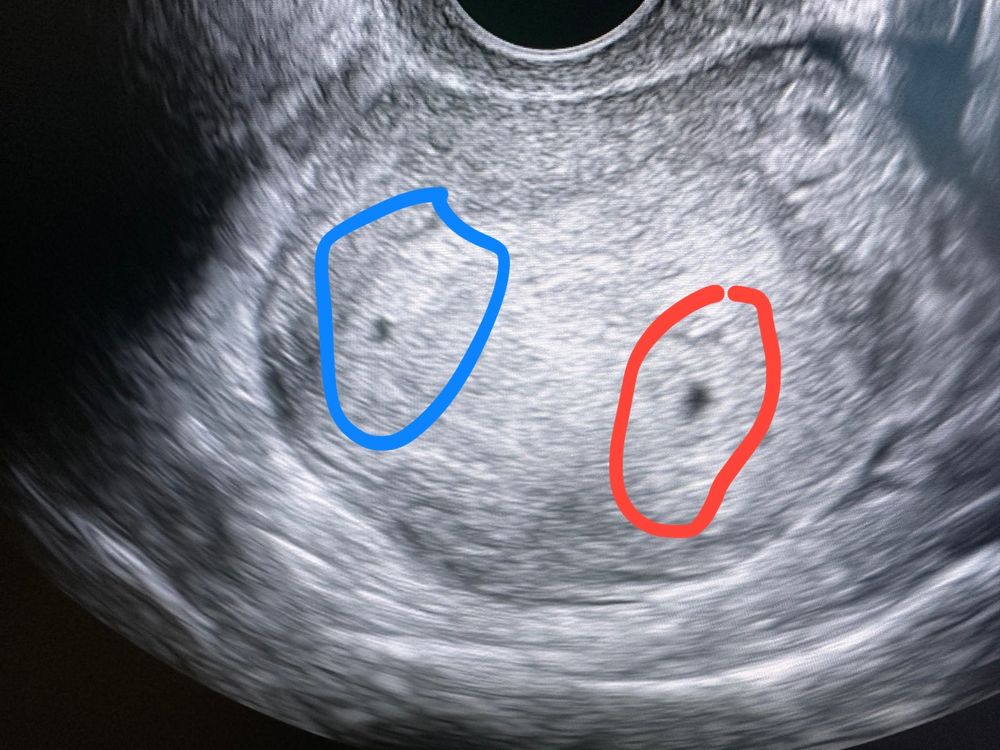

Два плодных яйца на Узи 5 недель

Это точно не может быть из одной яйцеклетки. Так как если из одной, то они не могут быть так далеко друг от друга... Может быть двойная овуляция в одном яичнике, даже не знаю как тогда жт должно быть. Ждём дальнейшее узи

Клепа, да я вот уже не знаю что это вообще такое. Узист сказала, что имплантационная засечка, возможно второе пя. Гинеколог посмотрела говорит это очаг эндометриоза вообще 🤷🏼‍♀️ поэтому до узи интрига полнейшая

Сейчас мама показала фото знакомому гинекологу, она сказала, что это вообще очаг эндометриоза, а не плодное яйцо, но откуда он там появился, две недели назад не было на узи ничего👀

Чаще всего из одной як получается монохориальная беременность (одна плацента на двоих), но может получиться и дихориальная (у каждого своя плацента), если деление эмбриона произошло до имплантации, это редко случается, но тем не менее бывает. По поводу размеров пя вам никто не сможет подсказать, всё очень индивидуально, может и догнать по размеру, может остановиться в развитии, на сроке до 12 недель сложно делать какие-либо прогнозы

Виктория, бывает два пя из одной ЯК,это когда яйцеклетка делиться в первые 72 часа,такие двойни-близнецы редкость,но бывает,если позже деление,то уже одно пя и два эмбриона